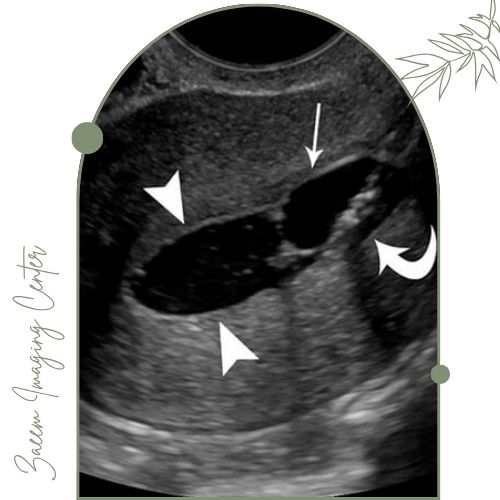

سونو هیستروگرافی (Sonohysterography) نوعی سونوگرافی تخصصی زنان است که به بررسی دقیق‌تر حفره رحم می‌پردازد. با تزریق محلول نمکی استریل (سالین) به داخل رحم و انجام سونوگرافی ترانس‌ واژینال تصویرسازی واضح‌تری نسبت به سونوگرافی معمولی امکان‌ پذیر می‌شود. این روش کاملاً غیرتهاجمی، سریع و بدون درد بوده و با دقت بالا بیماری‌ها و مشکلات داخلی رحم مانند پولیپ، فیبروم، چسبندگی، توده‌ها و خونریزی‌های غیرطبیعی را ارزیابی می‌کند.

در سونوگرافی ترانس‌ واژینال معمولی فقط ساختارهای رحم و تخمدان‌ها از طریق امواج صوتی بررسی می‌شوند. اما هیستروسونوگرافی با تزریق سرم به داخل حفره رحم دیواره‌های داخلی رحم را جدا کرده و اجازه مشاهده جزئیات، نقاط چسبندگی یا ضایعات کوچک را می‌دهد. این مسأله باعث می‌شود تشخیص پولیپ، فیبروم ساب‌ موکوزال، چسبندگی یا ناهنجاری‌های ساختاری رحم بسیار دقیق‌تر انجام گیرد.